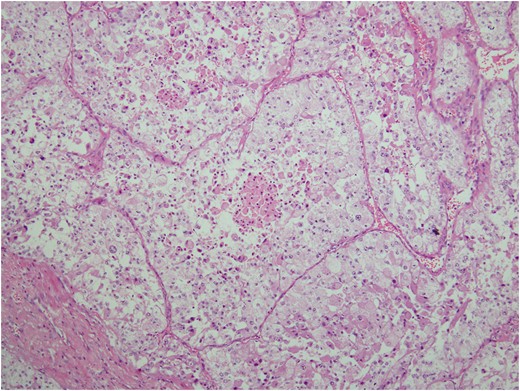

Histologic sections of the mass show distinct variably sized and shaped collections of uniform polygonal tumor cells, separated by fibrovascular septa and delicate capillary-sized vascular channels lined by flattened endothelium at low magnification (Fig. 5). Within the tumor nests, there is loss of cellular cohesion and necrosis of the centrally located cells in the nests results in the pseudo-alveolar pattern (Fig. 6). Vascular invasion is also present (Fig. 7). The individual tumor cells have distinct cell borders and abundant eosinophilic to clear, somewhat granular cytoplasm surrounding a central nucleus with variably sized nucleolus. Nuclear atypia is rarely seen. Mitotic figures are uncommon. The cells contain rhomboid or rod-shaped crystalline inclusions that are faintly apparent on routine histology and are better demonstrated with periodic acid-Schiff stain after diastase digestion (Fig. 8).

Tumor cells are arranged in organoid or nesting pattern. The nests are vary in size and shape and are separated by delicate thin fibrous septa containing vascular channels.

ASPS has a distinctive and characteristic, nested or organoid growth pattern. The nests tend to be uniform in size and shape, although some variations may be present. The nests are separated by delicate sinusoidal vascular channels lined by a flattened, single layer of endothelial cells. The cells may appear discohesive with focal necrosis in the center of the nests giving rise to the so-called, commonly seen, pseudo-alveolar pattern [6].